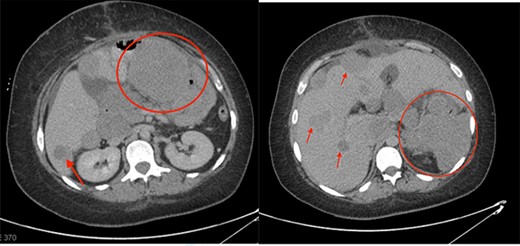

Investigations revealed an elevated WBC count of 35 × 10e9/L, a hemoglobin of 72 g/L and a CRP of 141 mg/L. A CT scan revealed a 15 × 11 cm multi-lobulated, heterogeneous, necrotic, exophytic mass arising from the stomach as well as multiple peritoneal deposits and five suspicious masses in the liver (Fig. 1). Upper endoscopy and liver biopsies were performed, and she was discharged home awaiting pathologic diagnosis. CT scan of her chest was negative for metastatic disease.

Initial CT scan showing large epigastric mass originating from the greater curvature of the stomach. Red arrow indicates large necrotic lymph node. Blue circles indicate liver metastases.